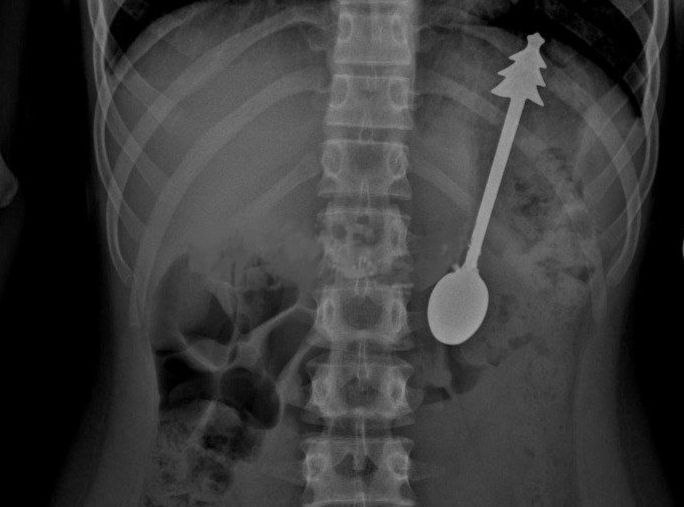

Проглотил ложку длиной 14 см оренбургские врачи без разрезов спасли ребенка В областную детскую больницу привезли мальчика который случайно проглотил металлическую ложку Врачи сразу сделали рентген Снимки показали что в желудке находится ложка длиной 14 см Ребенка срочно перевели в хирургическое отделение Операцию провели под общим наркозом Инородный предмет аккуратно достали с помощью эндоскопа Метод безопасный и не требует разрезов После операции ребёнок чувствовал себя хорошо Уже на следующий день его отпустили домой Советы для родителей если ребёнок проглотил посторонний предмет не паникуйте это только помешает действовать правильно не пытайтесь достать предмет сами так можно навредить ещё больше сразу вызывайте скорую или везите ребёнка в больницу Только врачи могут безопасно извлечь инородное тело Чем быстрее вы обратитесь за помощью тем лучше для ребёнка ВЕСТИ ОРЕНБУРЖЬЯ в telegram в MAX

Ребёнок случайно проглотил 14 сантиметровую ложку Детские хирурги срочно провели эндоскопическую операцию под общим наркозом и без необходимости разрезов успешно извлекли ложку из желудка Всё прошло без осложнений

Ребенок проглотил ложку длиной 14 сантиметров в Оренбурге Врачи областной клинической больницы провели обследование После чего они перевели ребенка в реанимацию и без разрезов удалили ложку из желудка После операции ребенок хорошо себя чувствовал его отправили домой на следующий день Подписаться на ТВЦ в MAX Ставьте профессионализму

Ребенок случайно проглотил 14 сантиметровую ложку в Оренбурге Его срочно доставили в больницу где провели операцию по удалению столового прибора с елочкой на ручке Все прошло успешно и уже на следующий день ребенка отпустили домой сообщили в местном минздраве Подписаться на РИА Новости